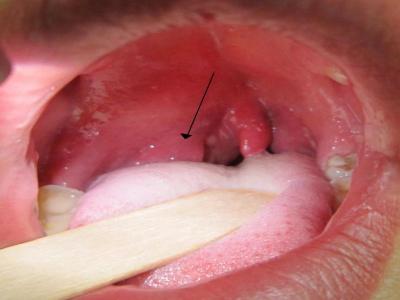

इसके शुरुआती चरण में गले के कैंसर का पता लगाना मुश्किल हो सकता है। हालांकि कुछ संकेत और लक्षण हैं जिनके जरिये इस बीमारी का पता लगाया जा सकता है और समय पर इलाज करवाया जा सकता है। इसके आम लक्षणों में वजन घटना, गले में खराश, लगातार अपना गला साफ करने की जरूरत होना, लगातार खांसी (खून खांसी हो सकती है), गर्दन में सूजन लिम्फ नोड्स, घरघराहट, कान का दर्द, आवाज बैठना आदि शामिल हैं। तीन ऐसे लक्षण भी हैं, जो बहुत कॉमन हैं-

गले में हमेशा खराश रहना यह कोई आम समस्या नहीं है। यह कैंसर की बीमारी का संकेत भी हो सकता है। अगर आपके गले में भी हमेशा खराब रहती है तो तुरंत डॉक्टर को दिखाकर जांच करवाएं।

गले में कैंसर की बीमारी होने पर वॉइस बॉक्स में स्वर ग्रंथियां प्रभावित होती हैं। जिसकी वजह से आवाज में बदलाव आना, गला बैठना आदि संकेत दिखाई देने लगते हैं। ऐसे संकेत दिखाई देने पर तुरंत डाक्टर से जांच करवाएं।

अगर आपको खाना निगलने में गले में दर्द या भारीपन महसूस होता है तो संभव है यह गले के कैंसर का संकेत हो। ऐसी स्थिति में आपको पानी पीने तक में परेशानी हो सकती है।

गले में कैंसर की स्टेज स्टेज 0: ट्यूमर केवल गले के प्रभावित हिस्से की कोशिकाओं की ऊपरी परत पर होता है। चरण 1: ट्यूमर 2 सेमी से कम है और गले के उस हिस्से तक सीमित है जहां यह शुरू हुआ था। स्टेज 2: ट्यूमर 2 से 4 सेमी के बीच है या पास के क्षेत्र में विकसित हो सकता है। स्टेज 3: ट्यूमर 4 सेमी से बड़ा है या गले में अन्य संरचनाओं में विकसित हुआ है या एक लिम्फ नोड में फैल गया है। स्टेज 4: ट्यूमर लिम्फ नोड्स या दूर के अंगों में फैल गया है।